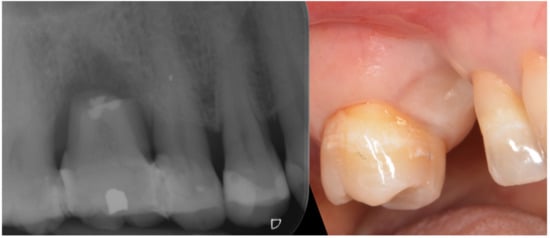

A 32-year-old female patient lost tooth 16 due to a fracture (Figure 5). After extraction, a significant defect in the edentulous ridge was evident also involving the distal of tooth 15 and mesial of 17. The pocket probing depth (PPD) at the distal of tooth 15 was 6 mm and the mesial of 17 was 7 mm.

Figure 5.

Broken tooth was splinted in place to favor healing of the soft tissue.

Three months after extraction the site was approached by means of GBR with the cortical lamina technique. Two periodontal probes were crossed to measure 7 mm of the vertical component, and 13 mm of the mesio-distal extension from bone peak to bone peak (Figure 6).

Figure 6.

Rx of the healed defect and its measurement.